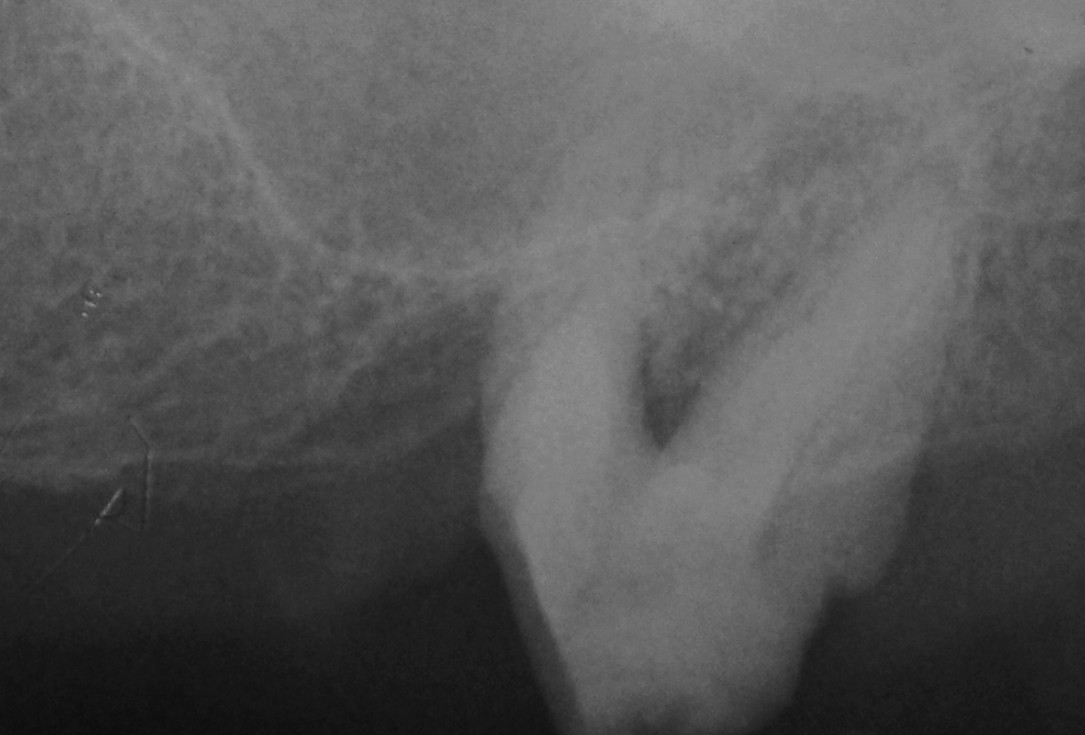

01/06 - Pre-operative radiograph.Treatment of a periodontal bone defect adjacent to an edentulous site using Straumann® Emdogain® - Prof. Dr. P. Windisch

Radiographic view before periodontal regenerative therapy with Straumann® Emdogain®. A deep intrabony defect appeared mesially and distally on the left mandibular first premolar. Pre-surgical probing measured 8 mm. The defect morphology presented as well-contained.